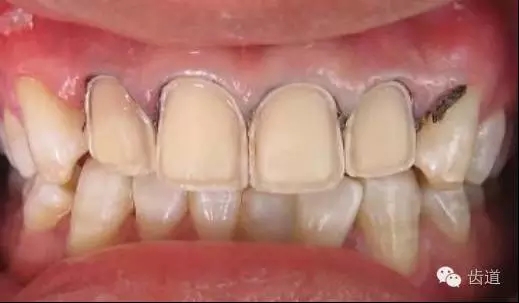

瓷貼面的牙體預備是影響修復效果的關鍵因素之一,適當的牙體預備可以為瓷貼面提供一定的空間,使修復后的牙齒外形美觀,患者感覺舒適,利于組織保健。

1、唇面預備:先用定深車針定出定深溝,再換合適車針磨除剩余的釉質。

唇面磨除的量依據所用貼面材料及牙齒的變色程度而定。

如下圖: